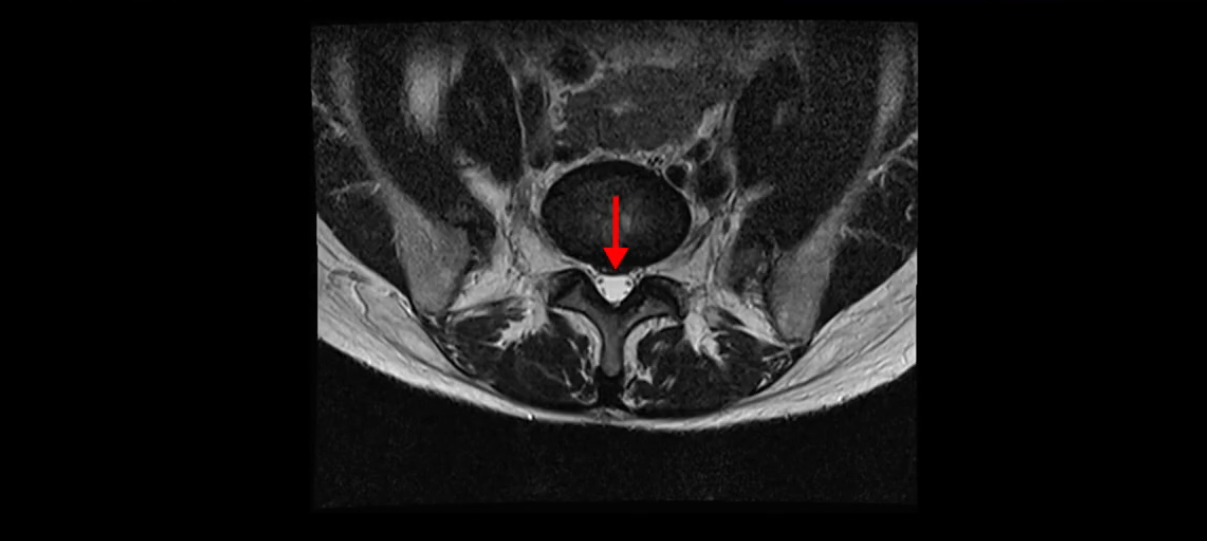

이분 MRI를 보시면 두 마디의 퇴행성디스크가 있습니다. 그리고 디스크가 조금씩 밀려 나와 있고요. 그런데 디스크 탈출 정도는 두 마디 다 심하지 않습니다. 4번 5번에는 디스크 탈출이 약간 있고,

척추관협착도 약간 진행이 되고 있고요.

5번 1번은 디스크 탈출이 가운데 쪽으로 살짝 있습니다.

중요한 것은 이 정도 경미한 탈출과 협착으로는 양쪽 다리가 저리고 아플 수가 없습니다.

이분 MRI를 보시면 퇴행성디스크가 있고 약간의 협착이 있지만 이 정도의 퇴행성디스크와 협착으로는 신경이 눌려서 양쪽 다리가 저리고 아픈 증상이 나올 수가 없습니다. 그래서 MRI와 이 환자분의 다리 증상이 매치가 안 된다고 하는 의사들이 많은 겁니다.